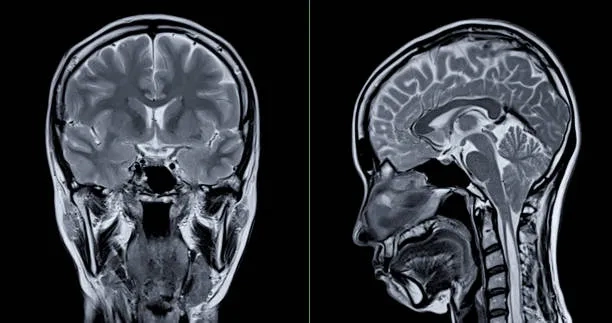

A brain scan comparison illustrating what is CTE